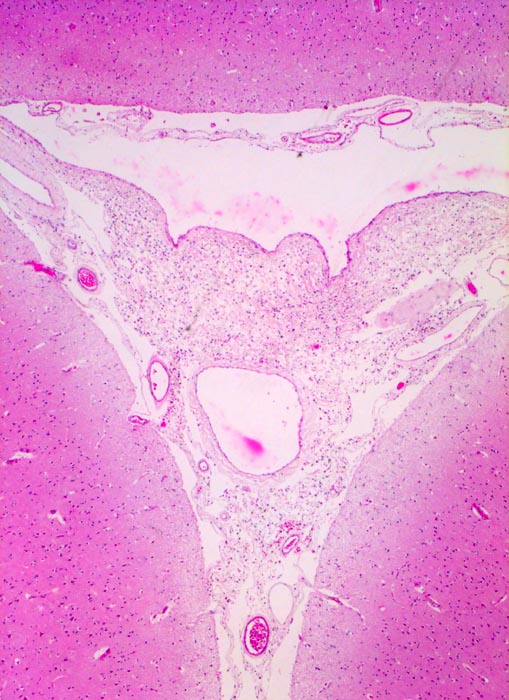

PathoPic ID 5223 - Leptomeningen und Subarachnoidalraum

Leptomeningen und Subarachnoidalraum

Normalbefund

Arachnoidea

Nervensystem

Die Hirnrinde wird bedeckt von den gefässführenden Leptomeningen.

Histologie

25